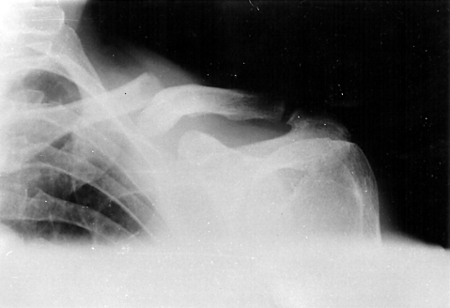

[Figure caption and citation for the preceding image starts]: Anteroposterior radiograph of left shoulder demonstrating a clavicle fractureAlao D et al. Emergency Medicine Journal 2005;22:232-3; used with permission [Citation ends].